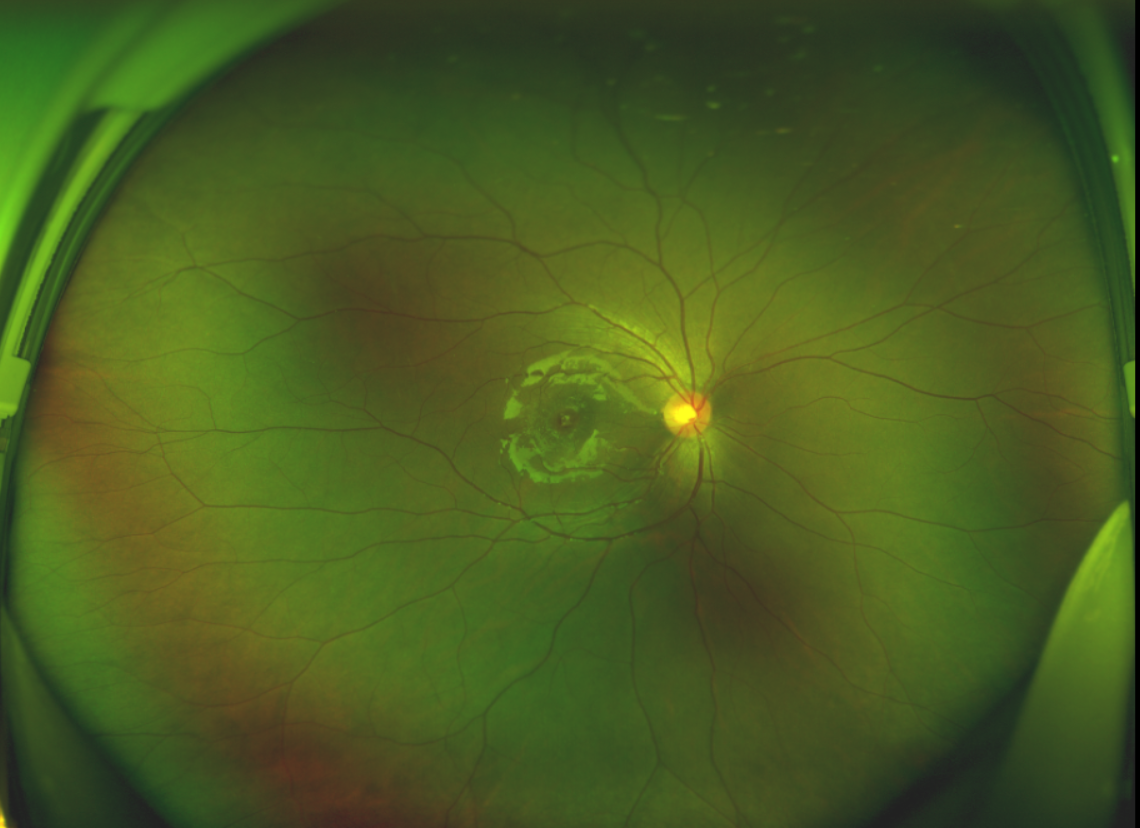

黃斑位于視網(wǎng)膜正中心,是視覺(jué)最敏銳的區(qū)域,堪稱“眼底的心臟”,負(fù)責(zé)我們閱讀、駕駛、識(shí)別人臉等精細(xì)視覺(jué)。 當(dāng)黃斑區(qū)的神經(jīng)組織出現(xiàn)全層缺損,形成一個(gè)“孔洞”,即為黃斑裂孔,它會(huì)直接導(dǎo)致中心視力急劇下降、視物變形、視野中心出現(xiàn)暗區(qū)。

除此之外,利用自體組織覆蓋為黃斑裂孔提供了理想的愈合環(huán)境,裂孔閉合速度顯著快于傳統(tǒng)方法。誠(chéng)誠(chéng)接受手術(shù)24小時(shí)后,檢查可見(jiàn)內(nèi)界膜瓣位置良好;術(shù)后1個(gè)月,黃斑裂孔已經(jīng)閉合,視力恢復(fù)到0.5;術(shù)后兩個(gè)月,視力進(jìn)一步提升到0.7。